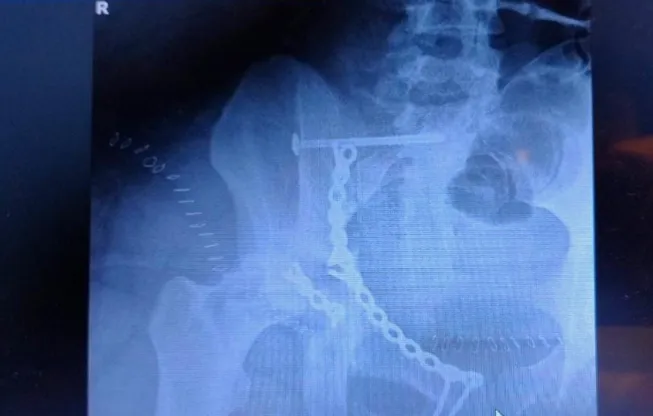

Realizaron tres cirugías traumatológicas de alta complejidad en el "Rene Favaloro"

El Hospital de Complejidad Creciente René Favaloro de Santa Rosa, incrementó significativamente la complejidad de sus prestaciones. Recientemente, un equipo mixto de trabajo, compuesto por especialistas de renombre internacional junto al equipo de traumatología del nosocomio público pampeano, realizó tres cirugías elevadas en complejidad a un paciente politraumatizado.